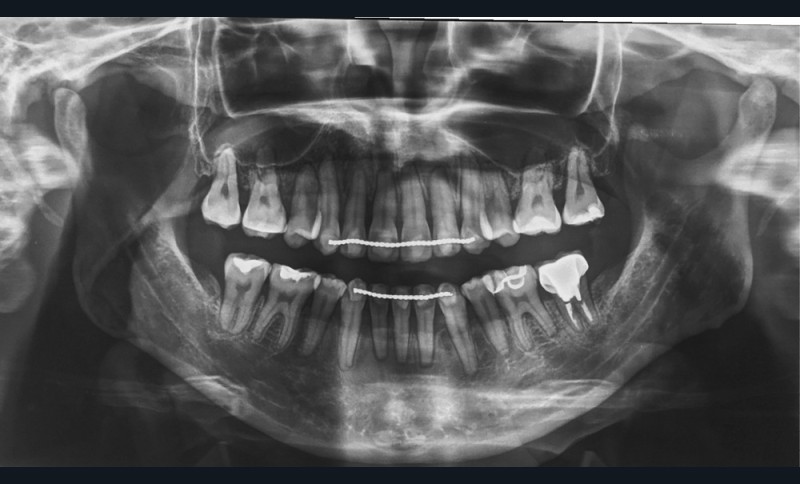

Sur le plan dentaire, la patiente est en classe III droite et gauche, canine et molaire de 6 mm, avec une occlusion inversée antérieure localisée à 11, 12 et 22. Elle présente une dysharmonie dents-arcades sévère, une agénésie d’une incisive mandibulaire est à signaler, et les troisièmes molaires ont été extraites à l’âge de 21 ans.

Un traitement en technique vestibulaire par appareillage multi-attaches .022 x .028 inch (prescription selon Roth) est entrepris, avec avulsion de prémolaires (15, 25, 34, 44).